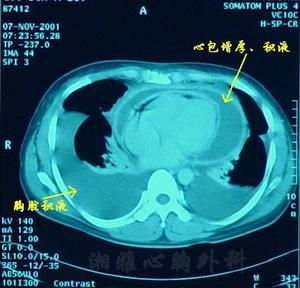

超聲心動圖:可發現少量心包積液。

一、確定有無心包炎 急性纖維蛋白性心包炎根據典型的心包摩擦音即可成立診斷,滲出性心包炎則根據上述心包積液體徵,心包填塞症狀和體徵結合X線、心電圖檢查一般不難作出診斷,尤其在普遍套用超聲心動圖後,對診斷心包積液有極高的準確性。

①心包穿刺術的術前準備:協助醫師做超音波檢查,確定積液的多少,並可指導選擇穿刺進針的部位、深淺和方向;向病人做好解釋,爭取病人合作,必要時給予鎮靜劑;術前準備好各種試管(包括培養皿及酒精燈等),以便留取標本送檢,並做好搶救物品的準備。